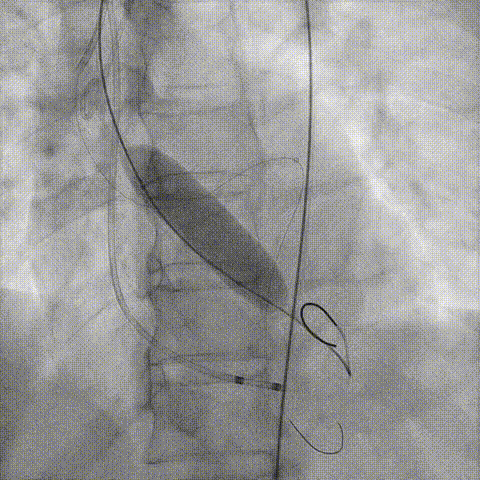

Telescope™+Runthrough

18mm*40mm 预扩张

预埋 Resolute Integrity 3.5*26mm

再次评估左冠开口